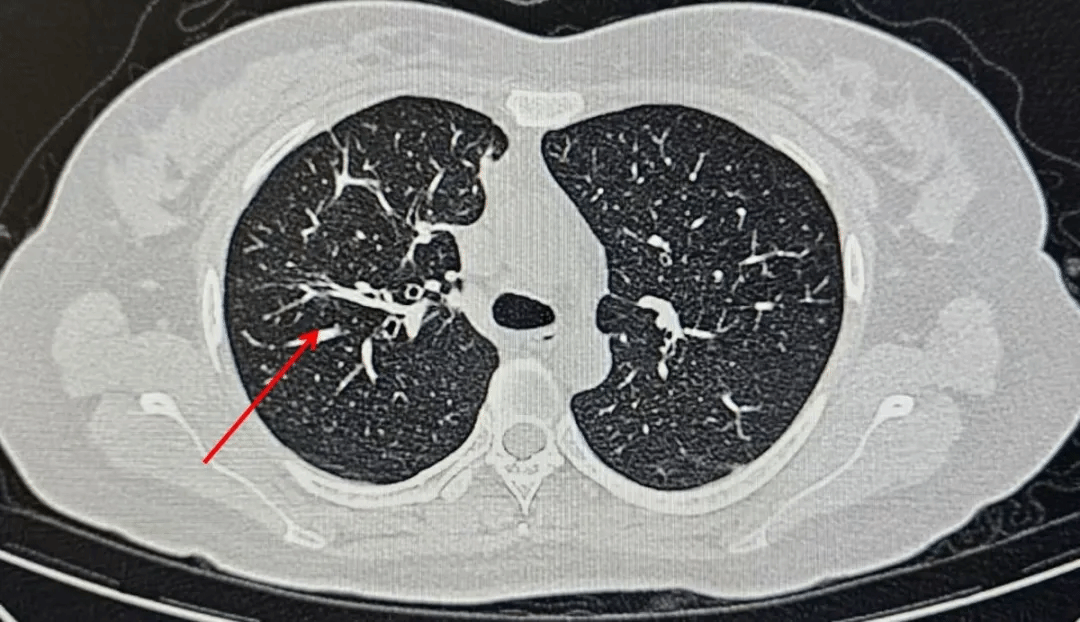

经过一段时间的规范抗真菌治疗,李女士的病情显著好转,复查胸部CT显示病灶明显吸收。目前李女士已出院,只需口服抗真菌药物并定期来门诊复查即可。